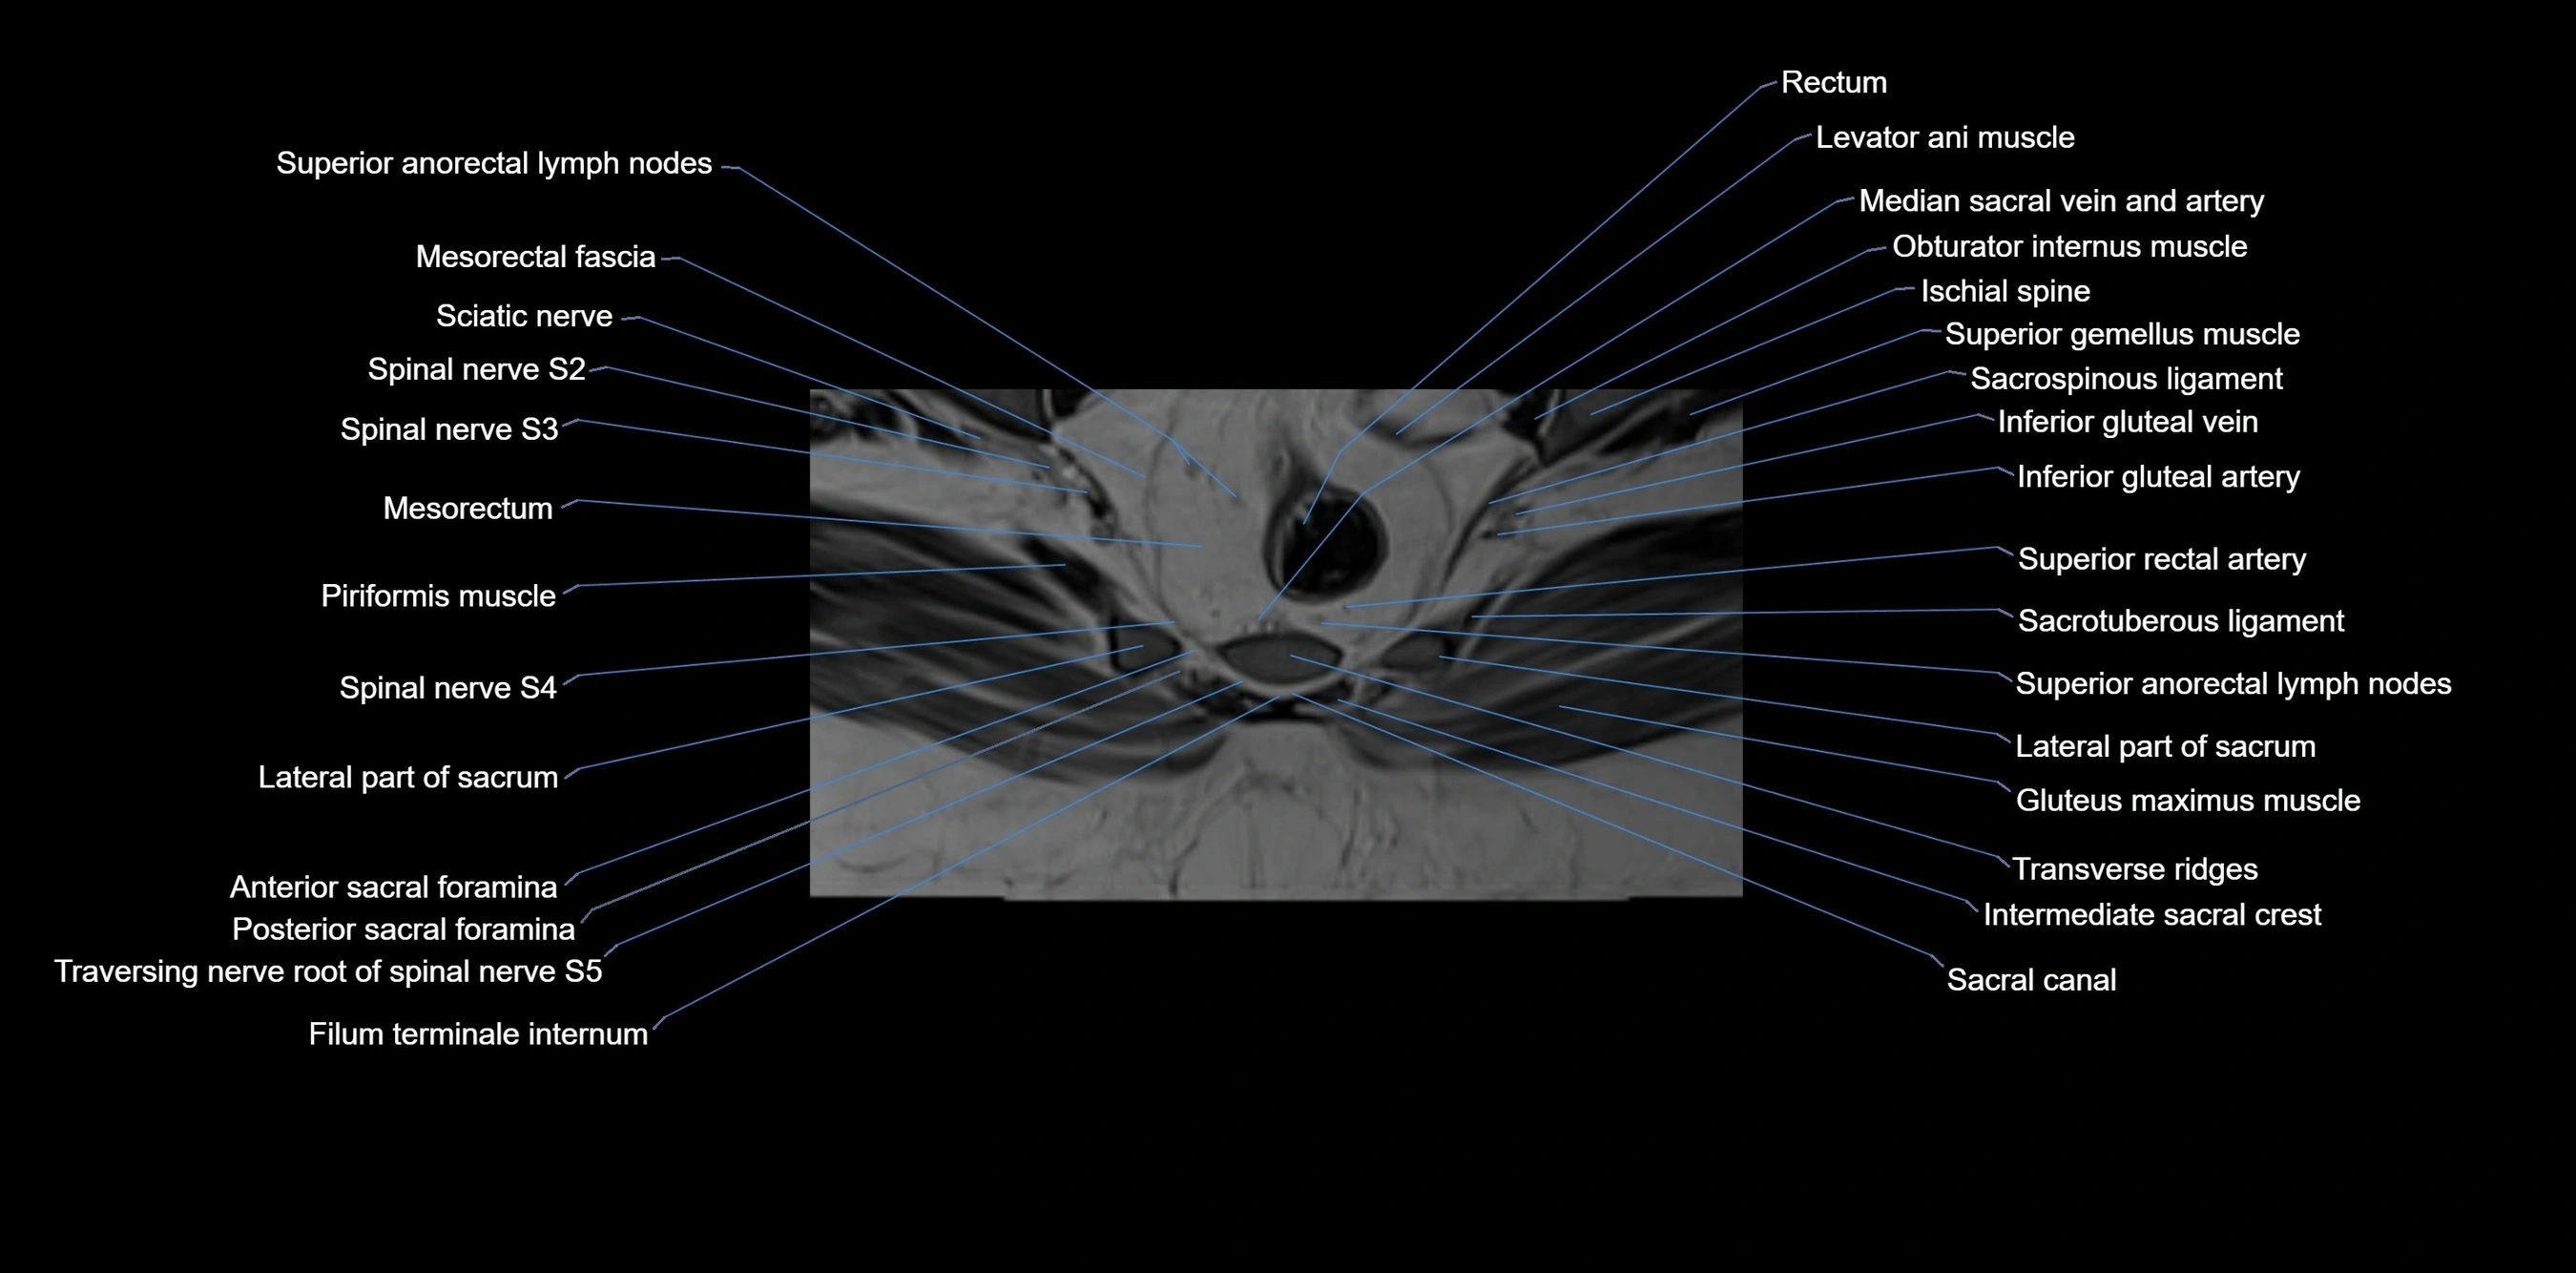

CT VRT image

image